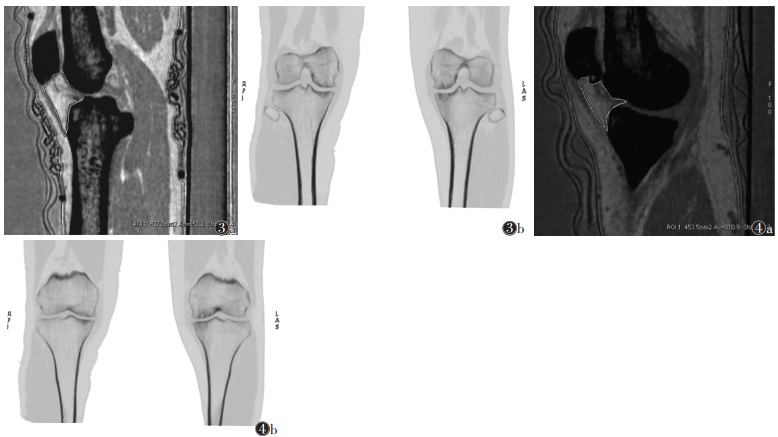

2.2 不同中医证型KOA的能谱CT定量参数比较(表 2;图 3,4)| 表 2 3组能谱CT定量参数比较 |

![]() |

| 注:图3患者,女,65岁,左侧KOA寒湿痹阻证。图3a为脂肪(肌肉)基物质图像,示脂基物质含量低(651.2 mg/mm3),其内有较多脂肪含量低的区域;图3b为骨(脂肪)基物质冠状位图像,示内外关节间隙狭窄不明显。图4患者,女,67岁,左侧KOA气滞血瘀证。图4a为脂肪(肌肉)基物质图像,示脂基物质含量低(810.9 mg/mm3),其内有少量脂肪含量低的区域;图4b为骨(脂肪)基物质冠状位图像,示左侧膝关节内侧间隙狭窄明显,胫股内侧区面积较外侧区和右侧膝关节胫股内外侧区面积小 图 3-4 不同中医证型膝骨关节炎(KOA)的能谱CT图像 |

3组中医证型间矢状位IPFP最大面积及其常规CT值差异无统计学意义(均P>0.05);IPFP脂基物质含量A组<B组<C组,差异均有统计学意义(均P<0.05);关节间隙面积3组均为内侧间隙面积小于外侧间隙面积,差异均有统计学意义(均P<0.05)。外侧间隙面积3组间差异均无统计学意义(均P>0.05)。内侧间隙面积A组和C组之间差异无统计学意义,但均大于B组(均P<0.05)。3组骨赘评级差异均无统计学意义(均P>0.05)。